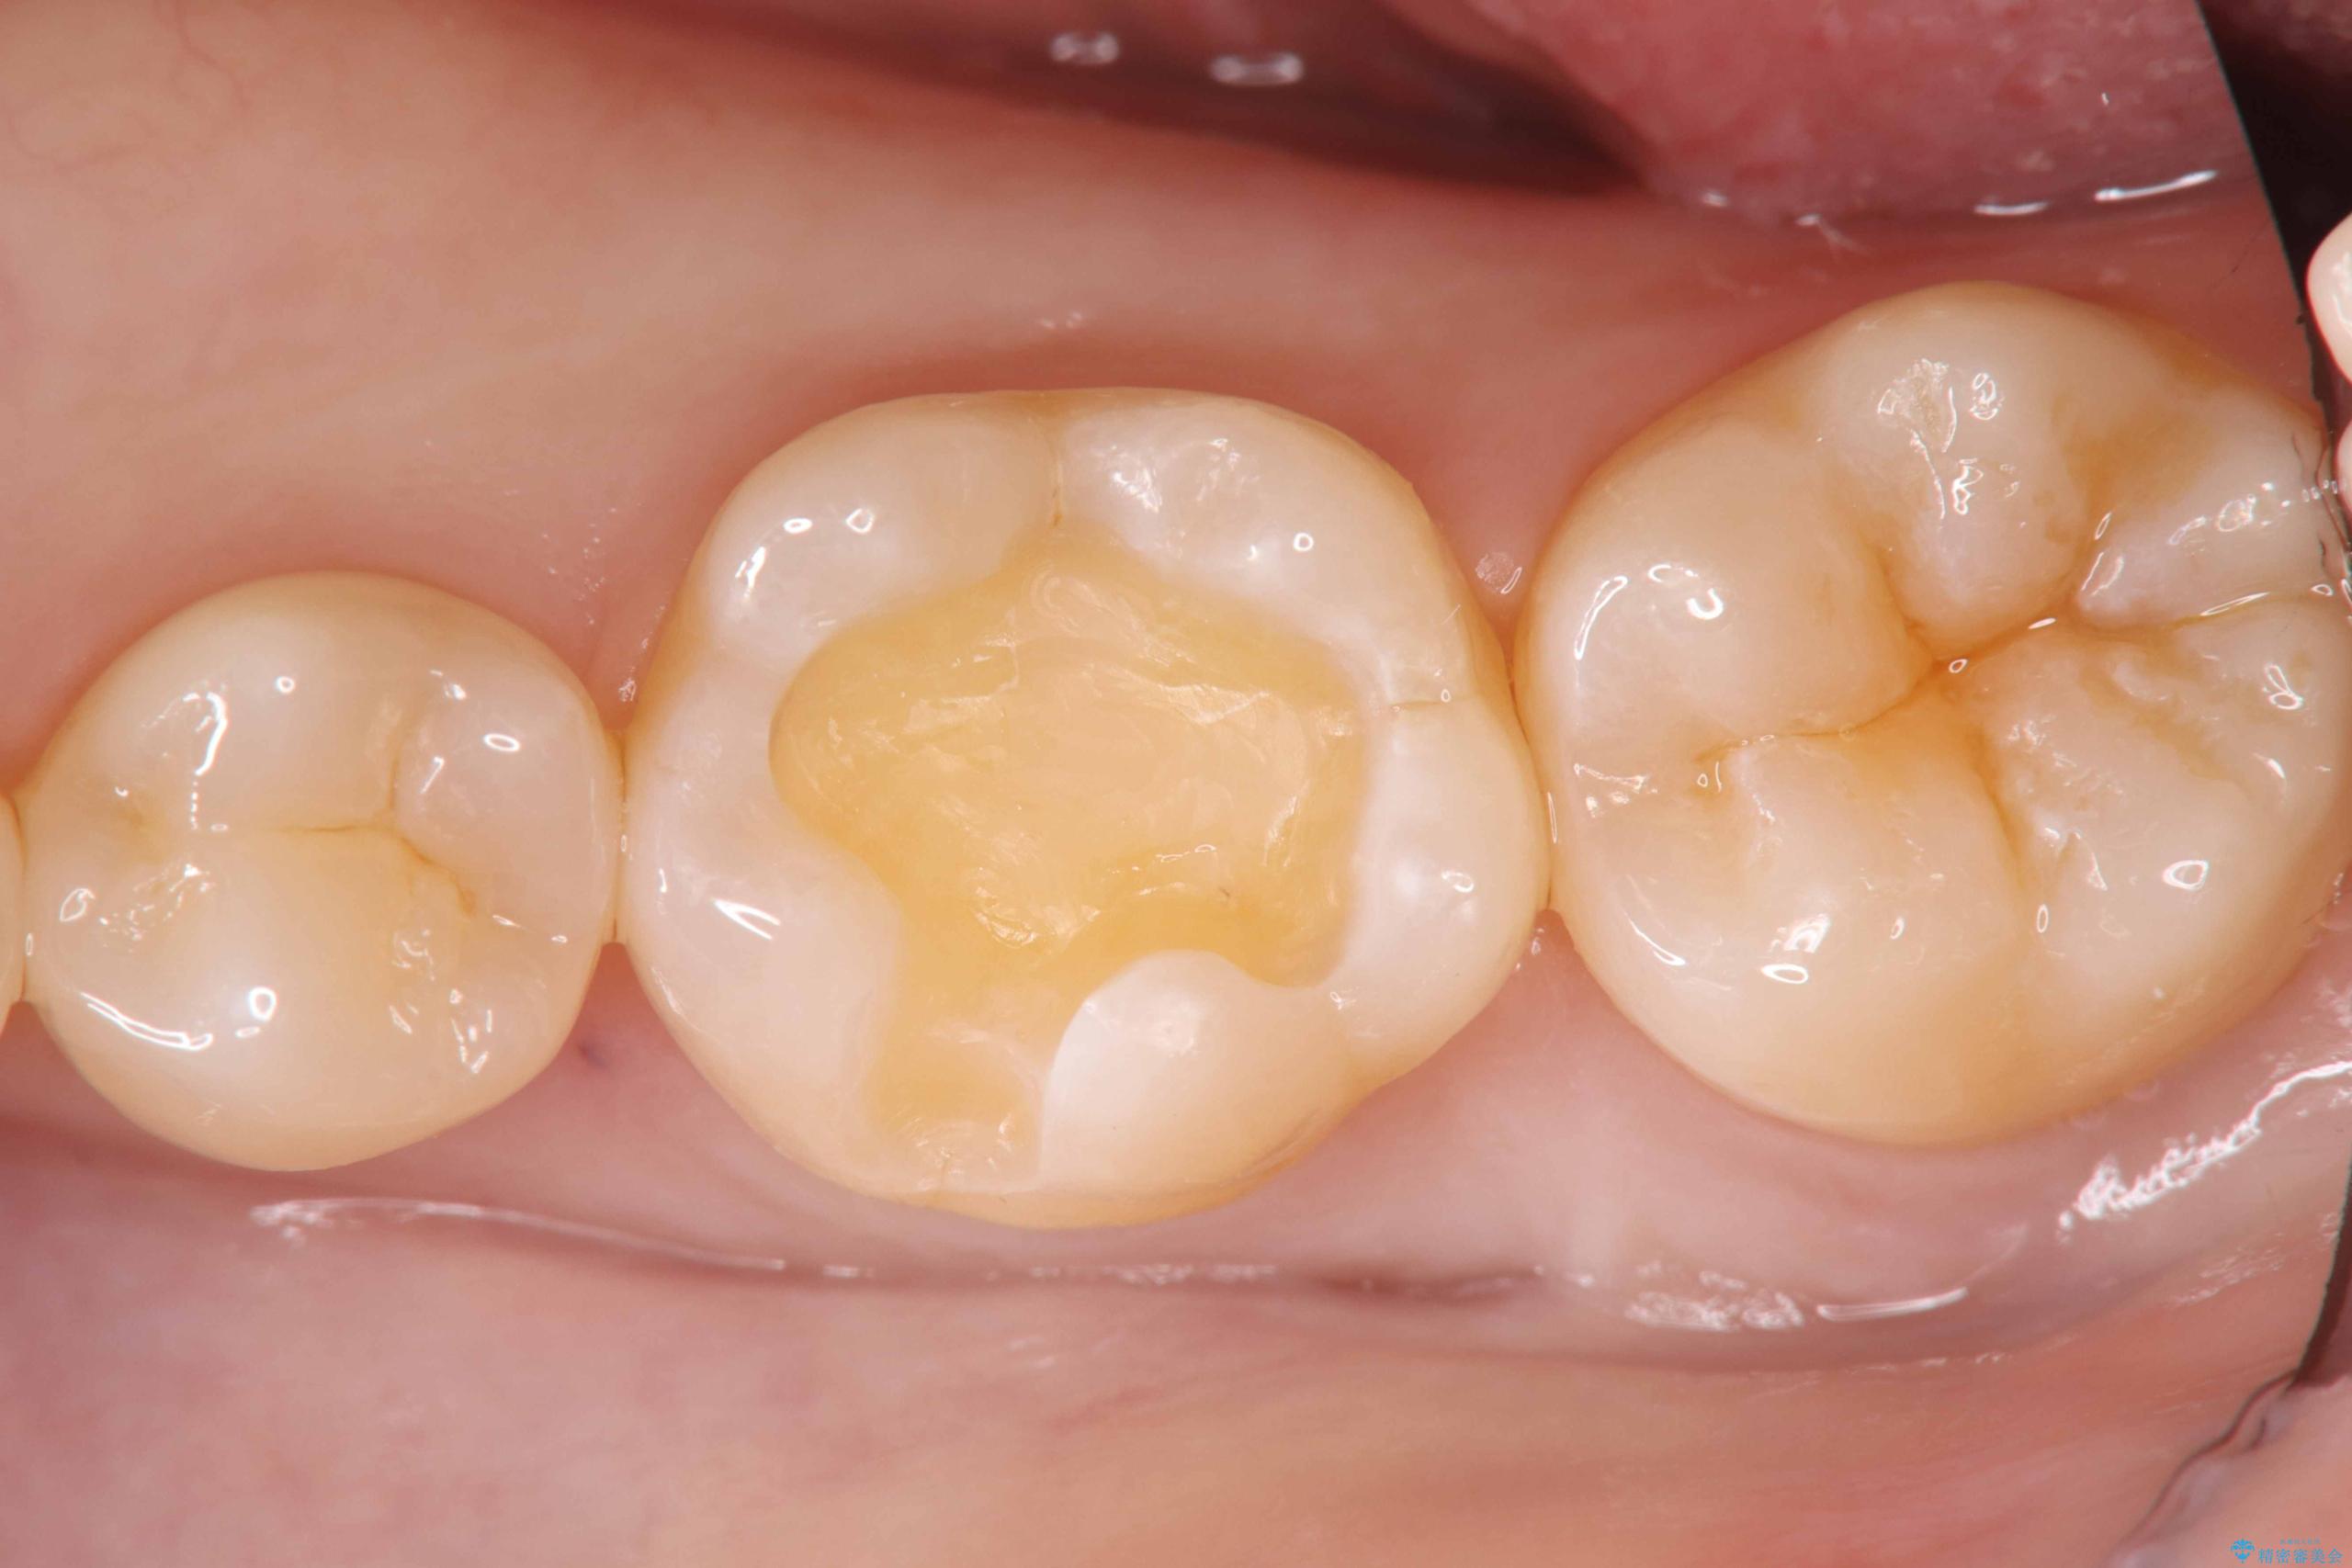

今回は、経年的な劣化が少なく、汚れが付着しにくいセラミックインレーを用いて治療を行いました。

セラミックインレー装着時には、唾液が入らないようラバーダムシートを使用し、接着精度を高めることで、長く安心して使っていただける治療を心がけています。